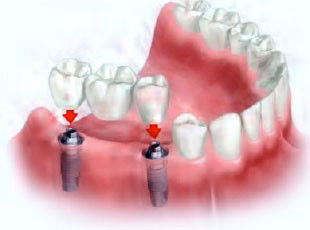

Prótese Múltipla Sobre Implantes (Ponte Fixa)